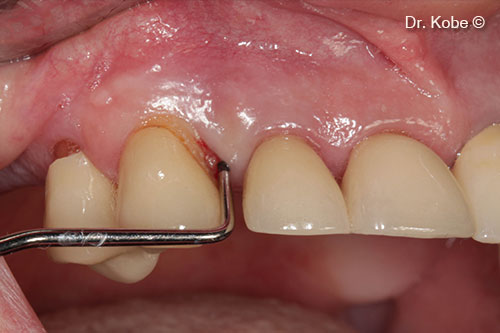

Access to the defect

Root surface cleaned